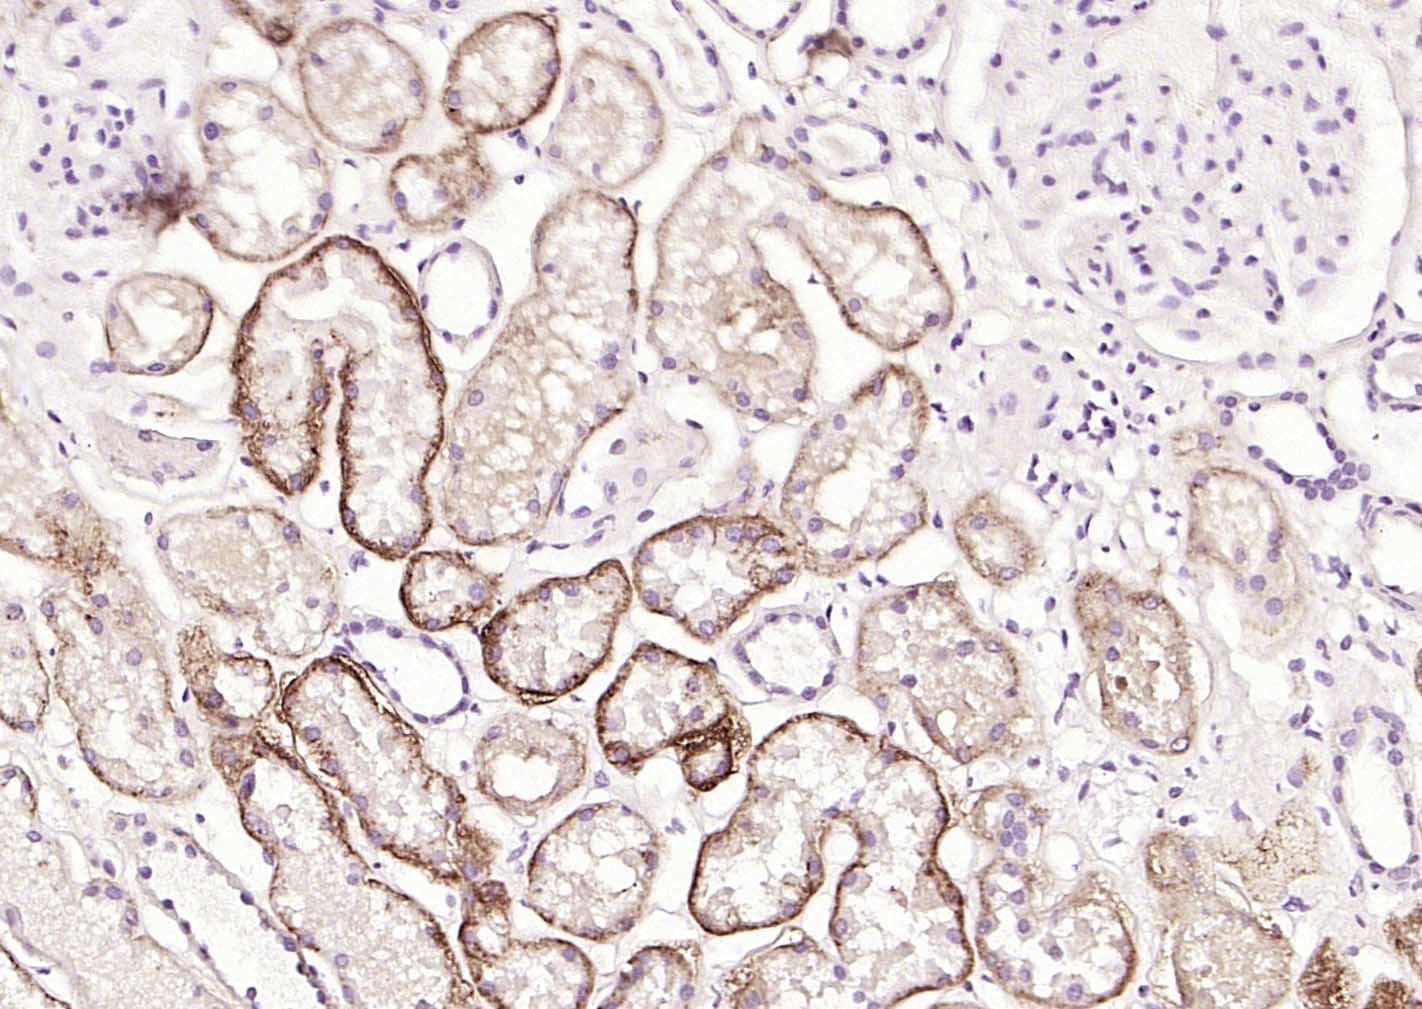

Paraformaldehyde-fixed, paraffin embedded (human kidney); Antigen retrieval by boiling in sodium citrate buffer (pH6.0) for 15min; Block endogenous peroxidase by 3% hydrogen peroxide for 20 minutes; Blocking buffer (normal goat serum) at 37°C for 30min; Incubation with (CD138) Monoclonal Antibody, Unconjugated (bsm-60902R) at 1:200 overnight at 4°C, followed by operating according to SP Kit(Rabbit) (sp-0023) instructionsand DAB staining.